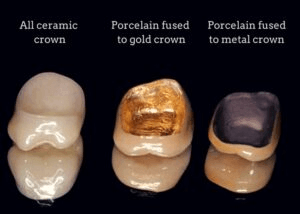

Types of Dental Crowns

Dental crowns come in several types, each with its own characteristics, advantages, and drawbacks. The most common types include:

What Materials Are Used for Dental Crowns?

Dental crowns can be fabricated from several materials, each with its own advantages and ideal indications. The most common types include: